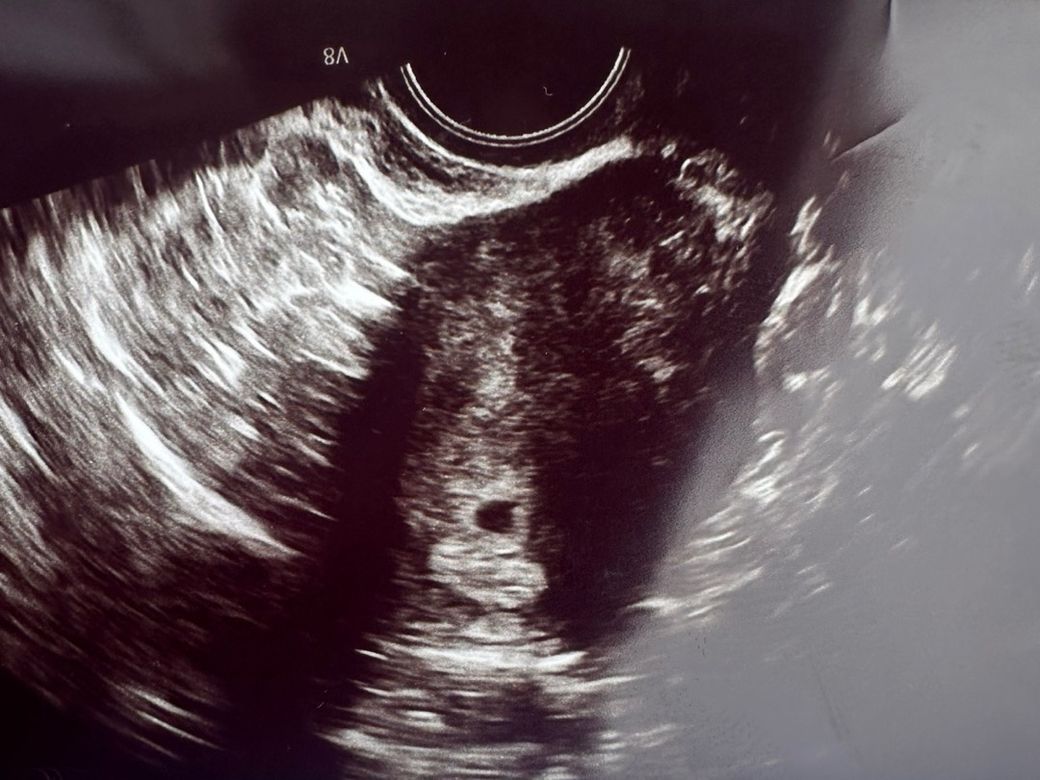

4월12일에(5주1일) 첫 초음파로 아기집 보고왔는데 이때 선생님이 담주에 오면 심장소리랑 들을수있다해서 오늘 갔다왔거든요

오늘 갔다왔는데 아기집 커지고 난황 봤어요

근데 심장소리와 아기는 못 봤네요 ㅠㅠ

6주1일에 심장소리 못듣는 사람 많은가요? ㅠㅠ 쌤이 불안하면 3-4일 뒤에 와보고 아니면 담주에 오라했는데 ㅠㅠ 수요일에 다시 가보려구요 그땐 심장소리랑 아기 볼 수 있을까요? ㅠㅠ 그리고 아기집 크기랑 난황크기 어때보일까요? 둘다 넘 커보이지 않나요? 괜찮은건가요??

• 1번 째 사진

• 2번 째 사진

말로 물어보신 부분 답변 드리자면 6주 1일에 심장소리가 아직 들리지 않는 경우는 꽤 흔합니다. 일반적으로 아기의 심장 박동은 6주, 7주 사이에 관찰되기 시작하지만, 배란일이나 착상 시기의 차이로 인해 실제 아기 성장 주기가 며칠씩 차이 날 수 있어서 정확히 6주라고 해도 아직 심장박동이 보이지 않을 수 있어요.

특히 아기집(gestational sac)과 난황(yolk sac)이 잘 보이고 크기나 모양이 정상이라면, 임신이 건강하게 진행 중일 가능성이 높습니다. 의사 선생님이 3, 4일 후 또는 다음 주에 다시 보자고 하신 건 자연스러운 경과 관찰 방법이에요.

아기집과 난황의 크기에 대해서는 정확한 수치를 확인해야 좀 더 정확히 말씀드릴 수 있지만, 보통 임신 6주 초반이라면 아기집은 약 1.52cm, 난황은 3-6mm 사이로 보이는 경우가 많아요. 너무 크거나 이상하게 보였다면 의사 선생님이 따로 말씀하셨을 거예요.